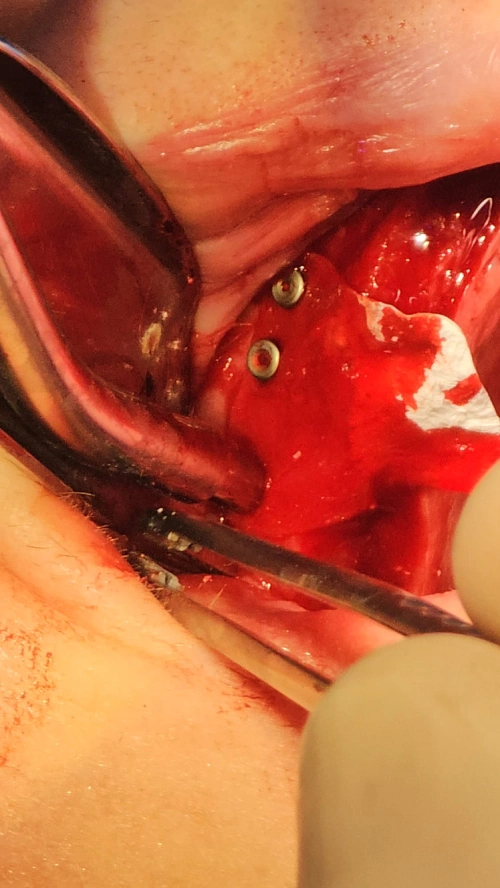

I¡¯ve used these membrane tacks in several cases now ¡ª love them and keep coming back for more